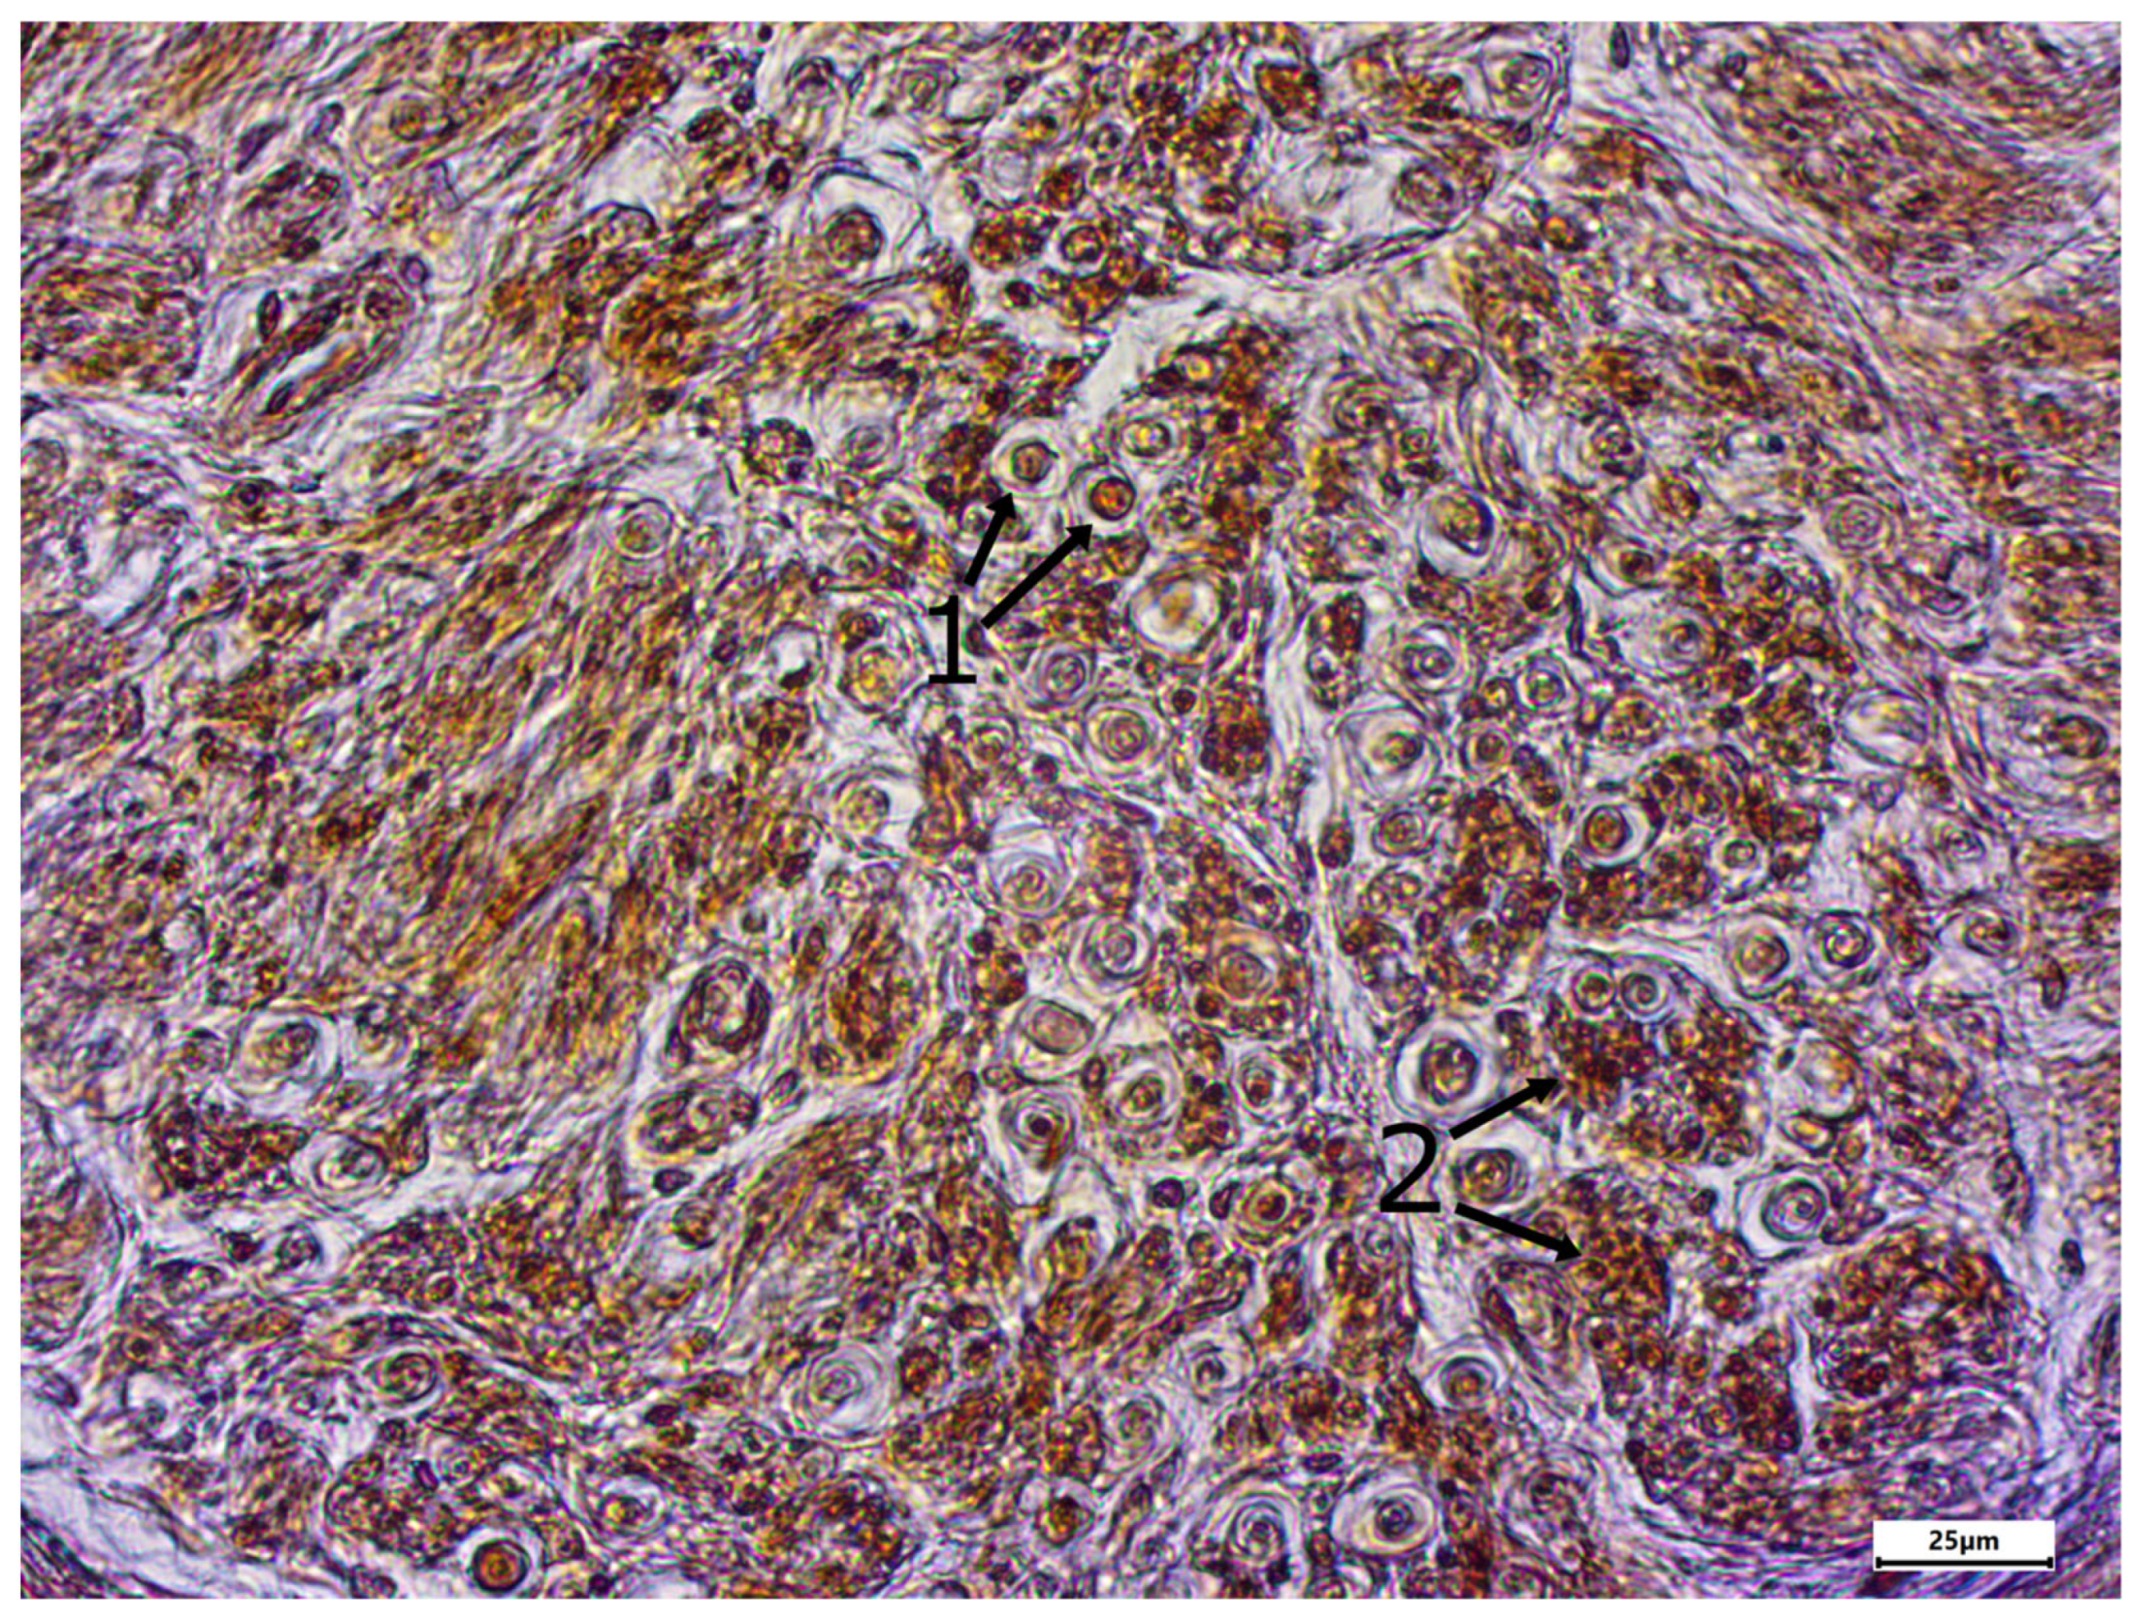

3. Results